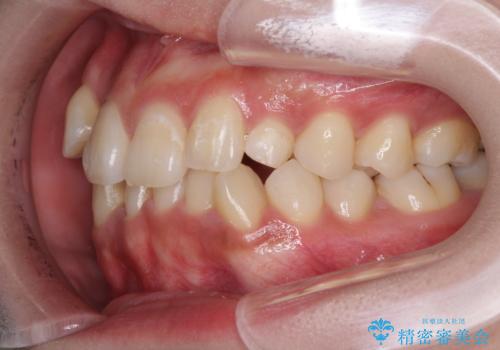

インプラント治療は当初の狙い通り、矯正治療期間中に行い、スムーズに処置を進めることができました。

歯並びが整ったことで治療前に認められた歯肉炎は全くなくなり、患者様には大変満足していただきました。